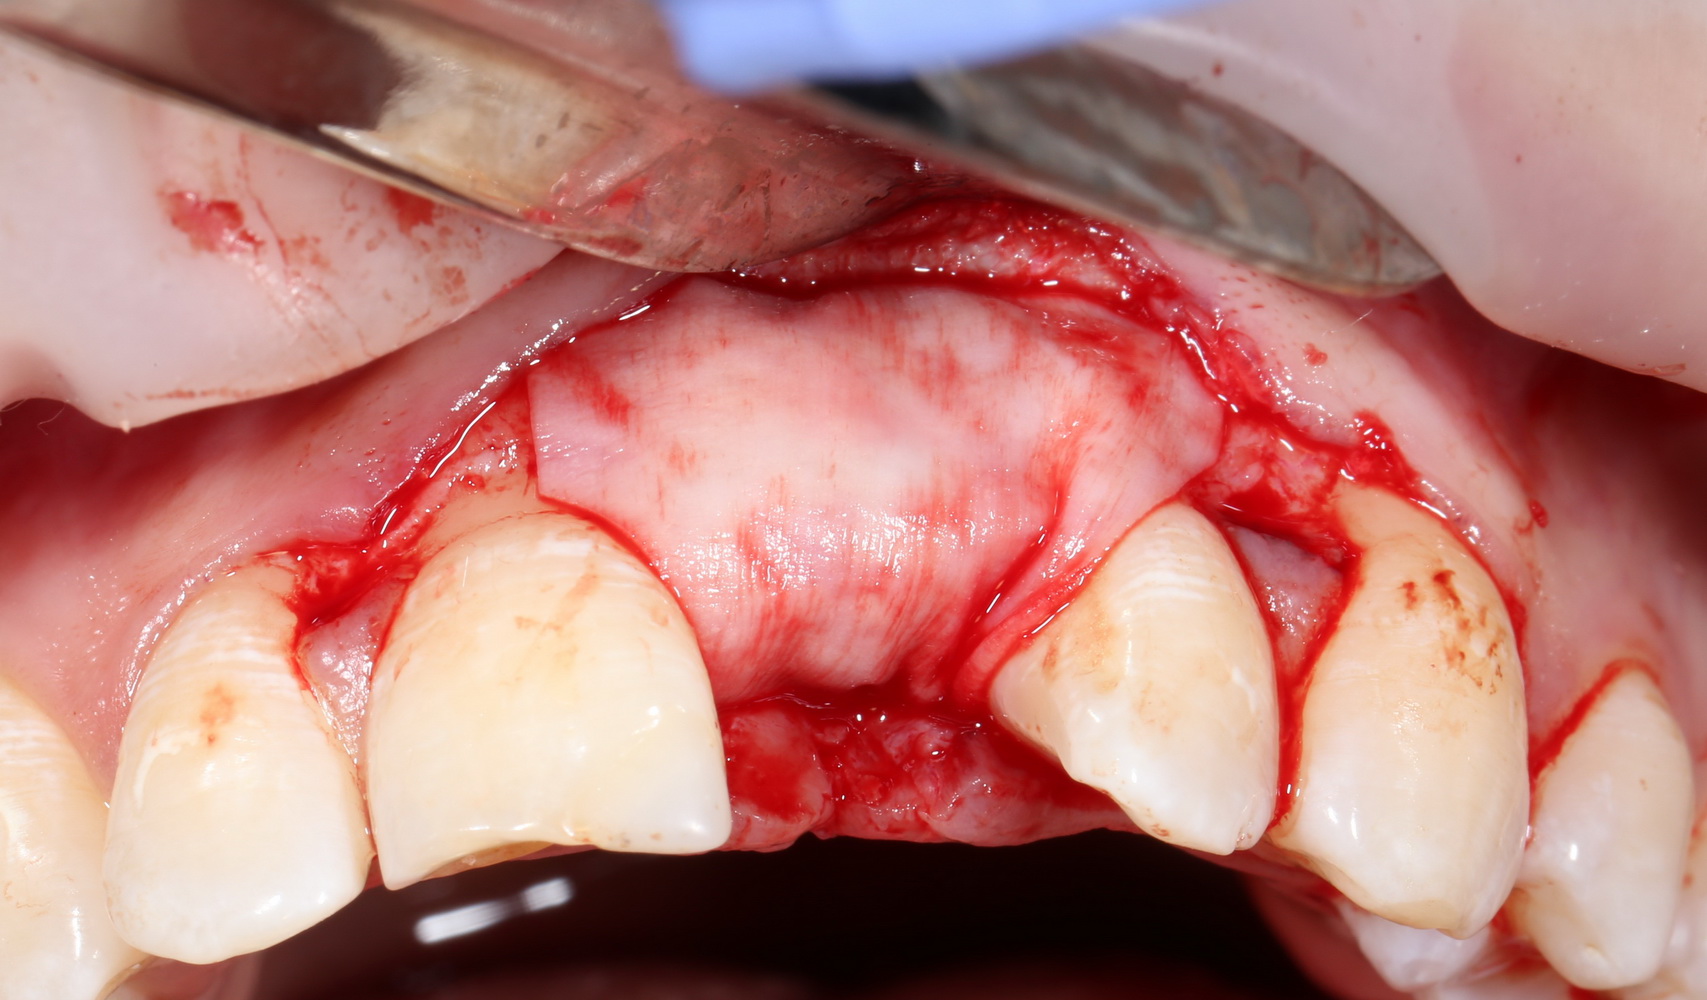

Операция начинается с разреза. Напомню, что разрез делается в пределах прикрепленной десны, это важно для последующего соблюдения Фактора успеха III:

A09A5444 (2)

Конечно, было бы легче сделать разрез по подвижной слизистой оболочке, но в последующем такой шов легко расходится и создать полную герметичность будет сложно.